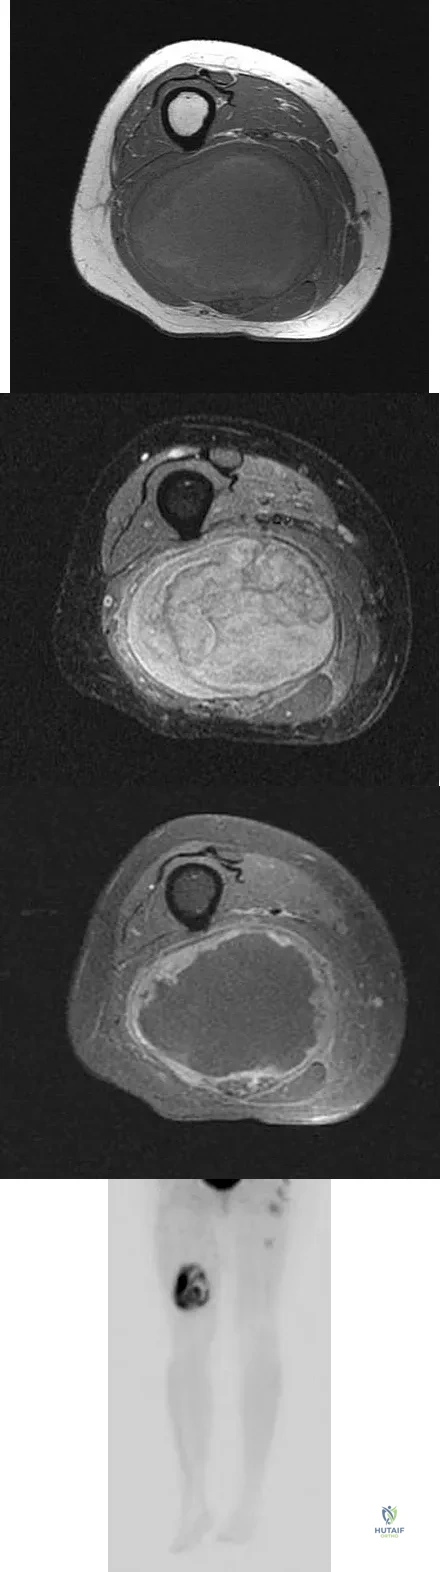

Figures 8a through 8c show the lateral radiograph and T1- and T2-weighted MRI scans of a 14-year-old soccer player who reports aching thigh pain. The next most appropriate step in management should consist of

Although the MRI findings could be misinterpreted as an aggressive soft-tissue process, the periosteal-based ossification on the radiograph in an athlete most likely suggests myositis ossificans. The radiograph should be repeated to see further maturation of the ossification with a typical "zoning" pattern. The zoning pattern is one of peripheral ossification. This is often best seen on a CT scan. King JB: Post-traumatic ectopic calcification in the muscles of athletes: A review. Br J Sports Med 1998;32:287-290.

Wang SY, Lomasney LM, Demos TC, Hopkinson WJ: Radiologic case study: Traumatic myositis ossificans. Orthopedics 1999;22:991-995, 1000.